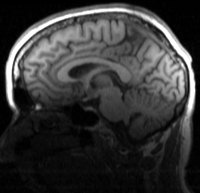

this is the fixed reference image. All images are aligned into this space this is the fixed reference image. All images are aligned into this space lleft lleft this is the T1 moving image

fixed image

T1 SPGR